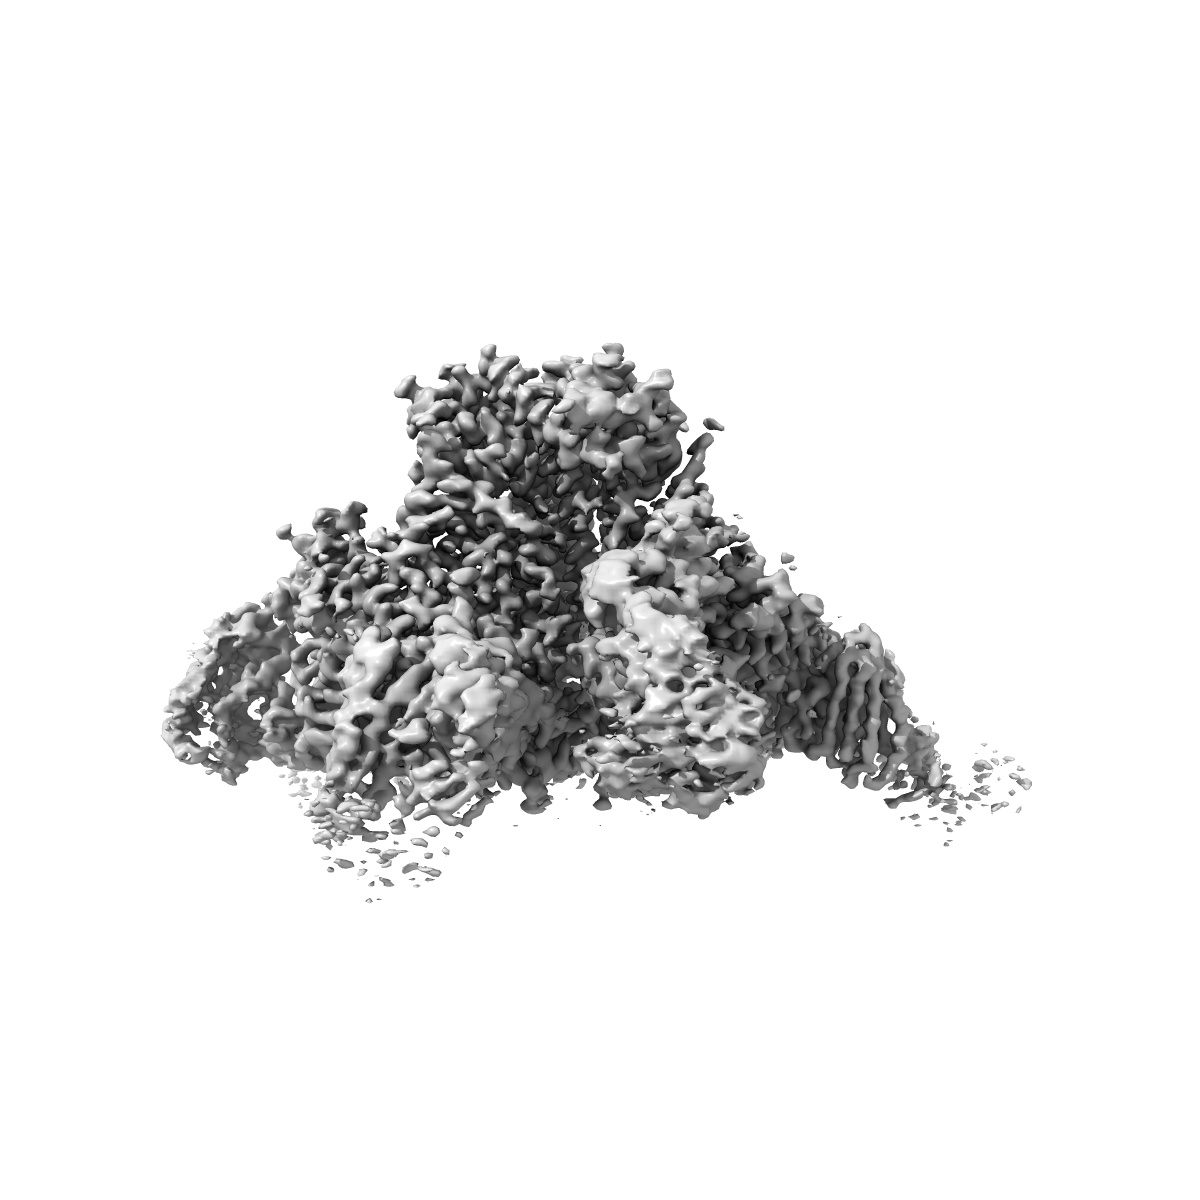

HIV-1 Env (BG505 SOSIP.664) in complex with the IgA bNAb 7-269 and the antibody 3BNC117.

Single-particle2.8 Å

Sample: Ternary complex of HIV Env (BG505 SOSIP.664) with bNAbs 3BNC117 (IgG Fab) and 7269 (IgA Fab)